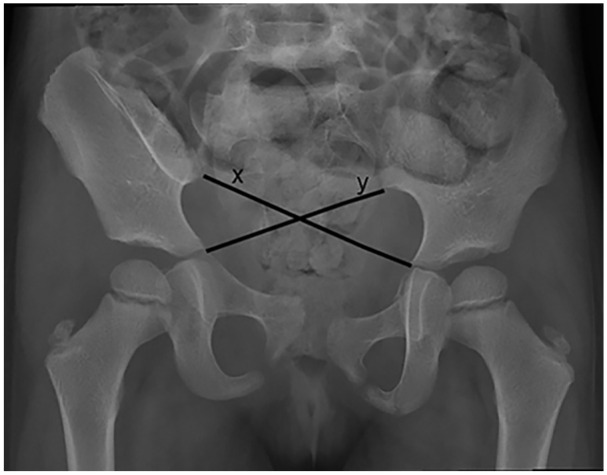

Purpose: We retrospectively analyzed the data of patients who underwent external fixation treatment for unstable pelvic fractures and evaluated the clinical effects of this treatment and factors influencing pelvic function recovery. Methods: The data of patients with unstable pelvic fractures treated with an external fixator between January 2006 and December 2018 were retrospectively analyzed. The analyzed parameters included demographic data, fracture healing, pelvic asymmetry, deformity index, and complications. Fractures were categorized using the Tiles classification. Pelvic function was evaluated using the Cole score. Pelvic risk factors were identified using univariate and multivariate logistic regression analyses. Results: Fifty-six patients (29 and 27 with type B and C fractures, respectively) were included. All fractures were healed at the time of the final follow-up. Nine and three patients had pin tract infections and loosened external fixators postoperatively, respectively. Pelvic asymmetry was reduced from 1.34 ± 0.15 cm to 0.70 ± 0.19 cm (p < 0.01), and the deformity index decreased from 0.13 ± 0.03 to 0.07 ± 0.02 (p < 0.01). The Cole score was excellent and good in 41 and 15 patients, respectively. Risk factors for pelvic function recovery included injury severity score > 25.5, age > 11.3 years, and lower-extremity fractures. Conclusions: External fixation is an effective method for treating unstable pelvic fractures in children, with the advantages of a simple operation, short surgical time, no interference with treatments for associated injuries, and avoidance of re-trauma caused by open reduction. An ISS > 25.5, patient age > 11.3 years, and associated lower-extremity fractures are predictors of pelvic function recovery. Level of evidence: Level IV.